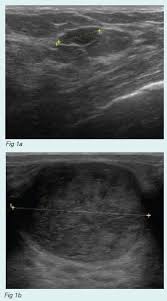

Ultrasound does not use or. 47 year old female presented with a painless but palpable left breast lump. Other ultrasound findings that suggest breast cancer include: We'll show you breast cancer pictures to help you identify any physical traits of the condition. Below are images of dcis on breast ultrasound. But radiologists can still see signs of cancer. What does breast cancer look like on a mammogram? Breast cancer is among the most common causes of cancer deaths today, coming fifth after lung, stomach, liver and colon cancers. Other ultrasound findings that suggest breast cancer include: The breast tissue kind of looks like waves on the ocean. Is tender, aches or feels painful. Ultrasound images are black and white, showing a small portion of the breast at a time. It is an infiltrating, malignant and abnormal proliferation of neoplastic cells in the breast tissues.

47 year old female presented with a painless but palpable left breast lump. The sound waves pass through the breast and bounce back or echo from various tissues to form a picture of the internal structures of the breast. But there are signs to look out for that could indicate something more serious. Inflammatory breast cancer pictures and symptoms. What does a cancerous breast lump look like on ultrasound? Inflammatory breast cancer is an infrequent, aggressive type of breast cancer that spreads rapidly. The person operating the ultrasound will sweep, or fan, the probe back and forth to look at different areas in 90 degree angle images. Generally speaking, the denser the tissue, the whiter it appears.